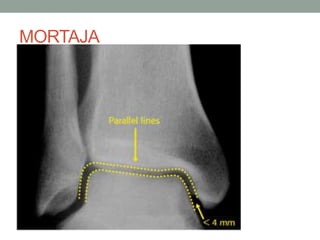

MORTAJA

(MORTAJA)